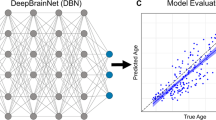

Piecewise left-null regression models were fit to each cerebrovascular biomarker across the lifespan to test the hypothesis that each cerebrovascular disease biomarker emerges at a given age, reflecting disease progression in adults with DS (Fig. 2). Enlarged PVS and the presence of infarcts were the biomarkers showing the earliest age-associated increase at 31 and 32 years old, respectively. Global WMH inflected at 35 years old. Regionally, frontal and parietal WMH inflected at 35 years old, while occipital WMH inflected later at 41 years old. In relation to traditional AD biomarkers, global amyloid and tau burden in early Braak regions, measured with molecular positron emission tomography (PET) imaging, inflected at 35 years old, after enlarged PVS scores. Then, tau burden in middle and late Braak regions inflected at 39 and 37 years old, respectively, after WMH.

Piecewise left-null regressions of (A) cerebrovascular biomarkers, (B) regional white matter hyperintensity volume, and (C) traditional AD biomarkers against age across the lifespan in adults with Down syndrome. Inflection point estimates, their 95% confidence interval, and their p-value are displayed at the top.